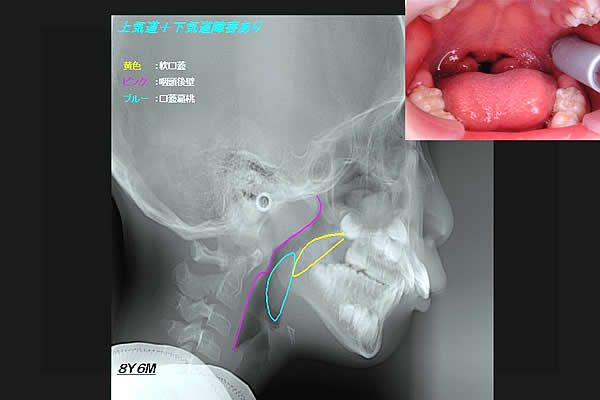

(図5)

鼻閉のため口呼吸をしている男児のX線側貌セファロ写真

鼻腔が曇っているから口呼吸を余儀なくされる。そのため直接外気が当たり、口蓋扁桃が腫脹している様子が見てとれる。青の部分であるそこで著しく気道が狭窄している。そうか!口呼吸をしている子ども達が、意欲に欠けるのは酸素の供給量が少ないためではないか・・・。扁桃腺の腫脹のため、咽頭部では酸素の通過障害が起きているに違いない。これでは、勉強どころではないな・・・。